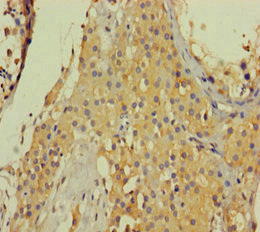

IHC (Immunohiostchemistry)

(Immunohistochemical analysis of Collagen 6 alpha 2 staining in human lung cancer formalin fixed paraffin embedded tissue section. The section was pre-treated using heat mediated antigen retrieval with sodium citrate buffer (pH 6.0). The section was then incubated with the antibody at room temperature and detected using an HRP conjugated compact polymer system. DAB was used as the chromogen. The section was then counterstained with haematoxylin and mounted with DPX.)